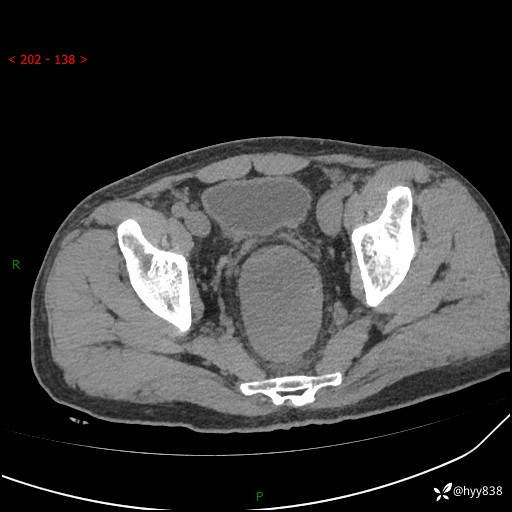

盆腔CT平扫+增强